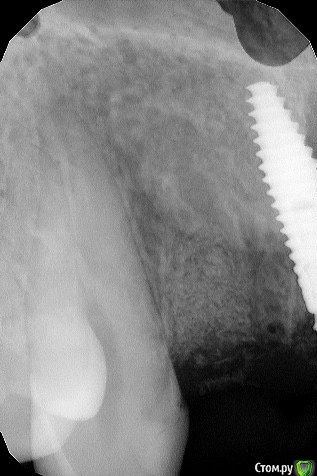

maksimstom Опубликовано 30 октября, 2020 Автор Поделиться Опубликовано 30 октября, 2020 27.10.2020 в 23:15, Irouil сказал: Покажите снимки, но, ИМХО, с таким дефектом ничего не получится скорее всего Кт после и прицелы области 1.2 и 2.2 Ссылка на комментарий

колесников Опубликовано 30 октября, 2020 Поделиться Опубликовано 30 октября, 2020 11,21 щит? Отлично! ,но нужно фланец делать и желательно имплант более небно. 22 следовало консервацию лунки сделать,теперь надо спасать 21,22,23 Ссылка на комментарий

maksimstom Опубликовано 30 октября, 2020 Автор Поделиться Опубликовано 30 октября, 2020 11,21 щит? Отлично! ,но нужно фланец делать и желательно имплант более небно. 22 следовало консервацию лунки сделать,теперь надо спасать 21,22,23 щита нет, ксено там. Консервировал 22, на прицеле с Графтом это 22. Фланец сдт? Ссылка на комментарий